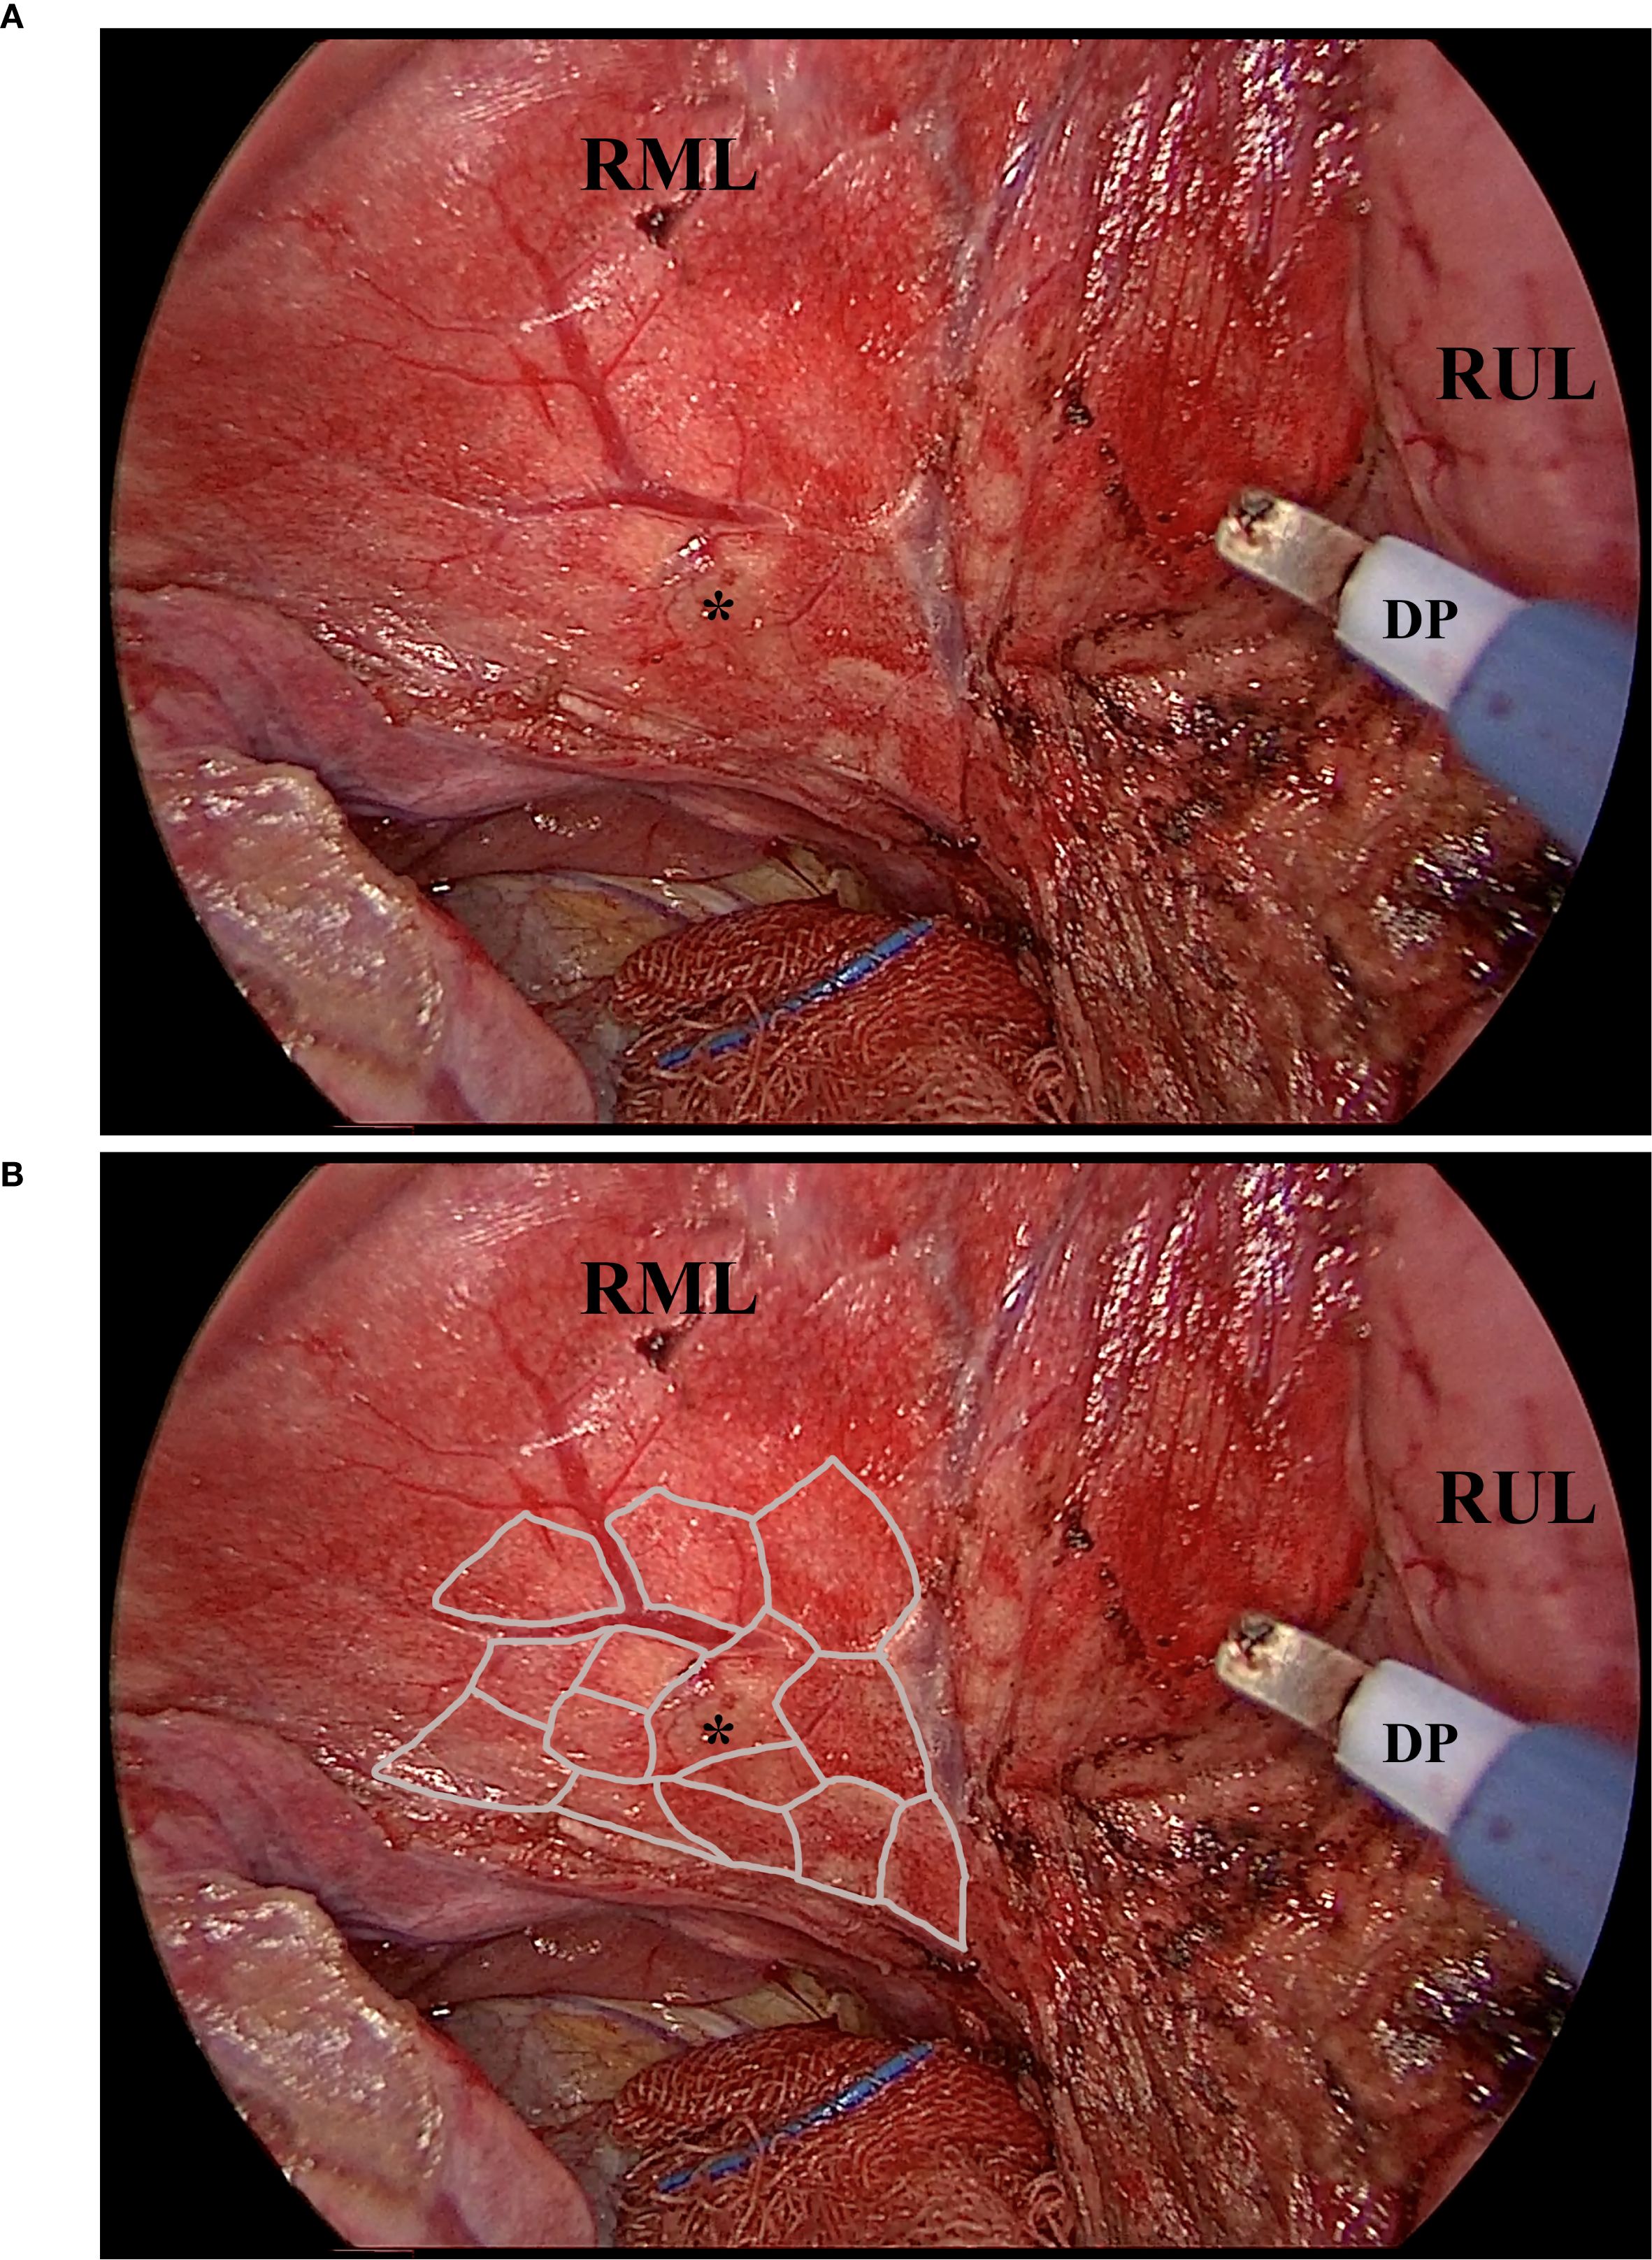

Two core strategies were applied to improve margin control and geometric precision. First, the resection was performed using a fine electrocautery pen rather than a linear stapler, providing enhanced maneuverability and contour adherence. Second, a “map zooming” concept was used: the target lung is expanded via bilateral ventilation (tidal volume 5 mL/kg), allowing for clearer visualization of lobular boundaries (Figure 2A). In cases with prominent interlobular septa, this expansion enables even lobule-oriented resections (Figure 2B).

Figure 2

Figure 2. The fully expanded parenchyma and the lobules. This picture, captured intraoperatively, shows the expanded parenchyma, the lobules, and the working diathermy pen. Noted that the diathermy pen was adjusted to an angle of about 40 degrees to facilitate instrument cooperation. (A), the exposed parenchyma of the right middle lobe after the right horizontal fissure was divided by the diathermy pen. The sub-fissure pulmonary vein was visible, as were the nodule-bearing lobules. (B), the illustrated margin of the lobules. Noted that the expanded parenchyma, plus the thin edge of the diathermy pen, made the lobule-based resection achievable. Asterisk, the nodule that is to be resected. DP, the diathermy pen. RML, the right middle lobe. RUL, the right upper lobe.